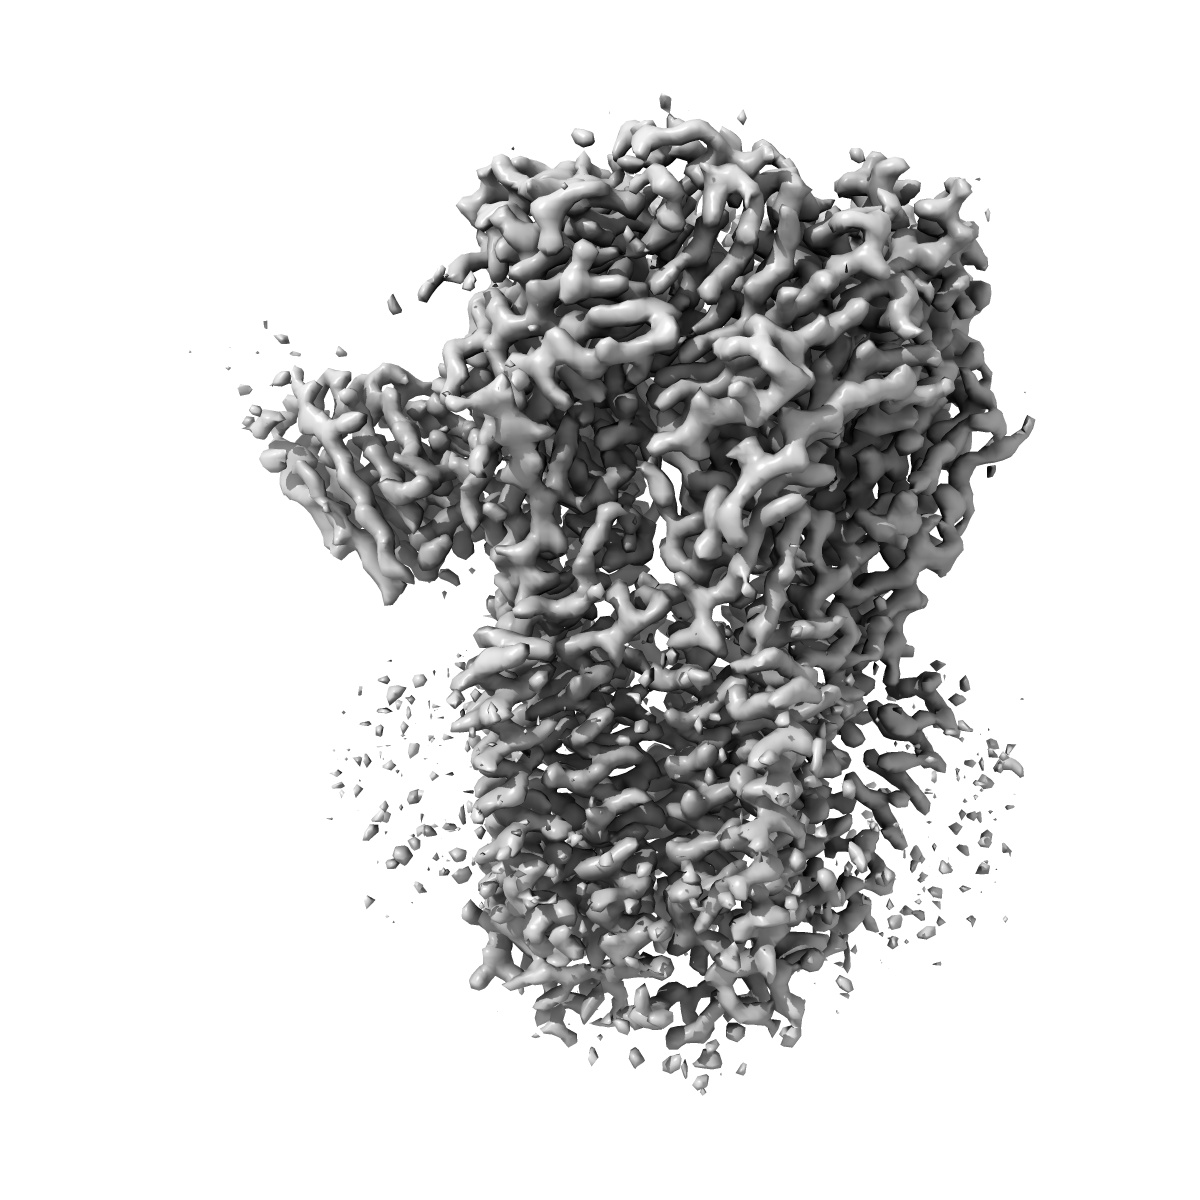

CryoEM structure of human full-length heteromeric alpha1beta3gamma2L GABA(A)R in complex with alprazolam (Xanax), GABA and megabody Mb38.

Single-particle3.26 Å

Sample: CryoEM structure of human full-length heteromeric alpha1beta3gamma2L GABA(A)R in complex with alprazolam (Xanax), GABA and megabody Mb38.

GABAAreceptor signalling mechanisms revealed by structural pharmacology.